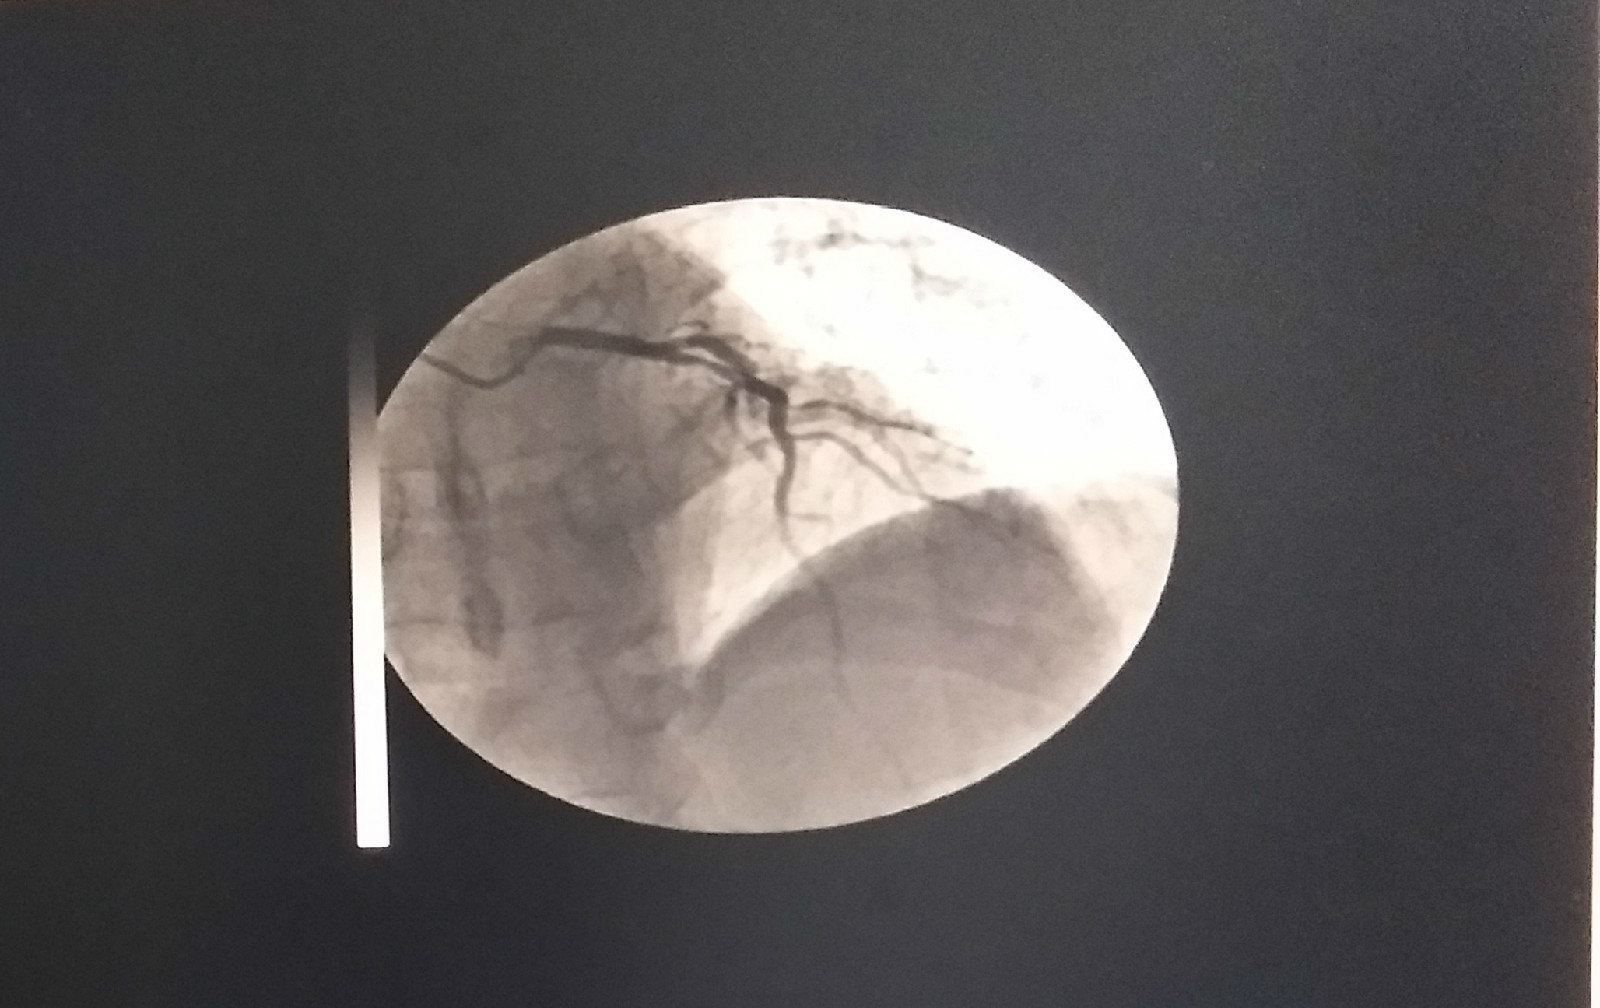

支架置入前前降支病变处!

手术前照片(前降支)